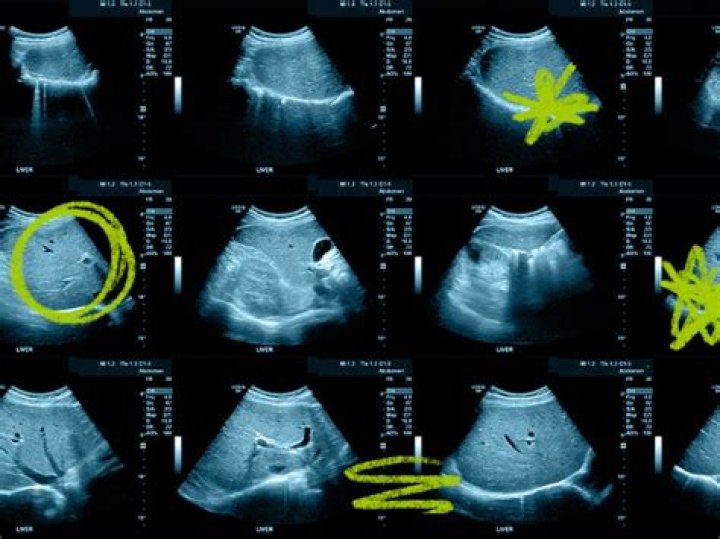

What will an ultrasound show in a dog?

Sonography has its limitations, but it can be very useful when looking at the organs that reside inside the abdomen. This includes the liver, gallbladder, kidneys, adrenal glands, stomach, intestines, spleen, bladder, prostate, uterus, ovaries, and numerous lymph nodes.

An abdominal ultrasound will allow your doctor to get a detailed look at their stomach and intestines, as well other associated structures. Maybe your pet has diabetes mellitus and they want to check for other health problems that may be impacting this disease.

Ultrasounds help us to look inside the bladder, the kidneys, the prostate or uterus. If your pet is having problems urinating, recurrent infections or bloodwork shows kidney problems or infection, an ultrasound can be invaluable. Ultrasound makes the diagnosis of a bladder tumor, for example, much easier.

What can an abdominal ultrasound detect in dogs?

An abdominal ultrasound enables your vet to have a closer look at the organs in the abdominal cavity such as the liver, kidneys, stomach, spleen, pancreas, adrenal glands, intestines, bladder, uterus, ovaries, prostate, and lymph nodes.